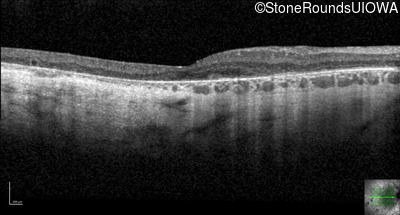

Optical Coherence Tomography - Left - 20/32 -2

Exemplar / OCT Stack